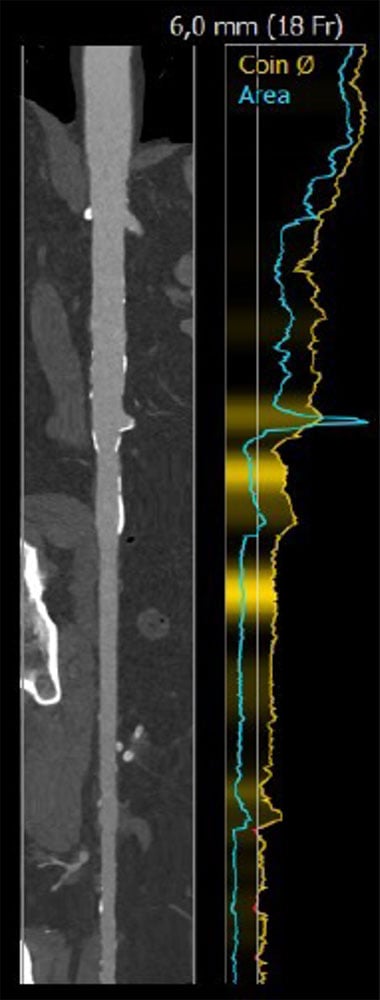

Case planning: CT

Annulus: 29.6 cm

LVOT: 32.2 cm

Moderate Ca2+, tricuspid